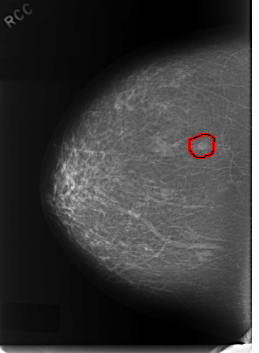

C_0331_1.RIGHT_CC

FILE: C_0331_1.RIGHT_CC.OVERLAY

TOTAL_ABNORMALITIES 1

ABNORMALITY 1

LESION_TYPE MASS SHAPE OVAL MARGINS CIRCUMSCRIBED

ASSESSMENT 3

SUBTLETY 5

PATHOLOGY BENIGN

TOTAL_OUTLINES 1

BOUNDARY